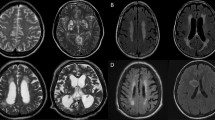

Active-tDCS simulation of brain current flow (M1-SO) is predicted to produce electric fields across the brain pain neuromatrix regions, including motor cortex, DLPFC, nucleus accumbens and cingulate (Fig. 2B).

(A) High-resolution computational model simulation of brain current flow during tDCS. The “M1-SO” assembly was simulated by sponge with anode positioned vertically over 10–20, location C3, and cathode positioned horizontally on the contralateral-supraorbital, approximately over 10–20, location Fp2. (B) Current flow patterns on a slice (A/m2). The model predicted electric field maps generated in outer cortical regions. Our results show diffuse and clustered brain current flow that includes left motor regions, as well as other regions implicated in treatment of pain and other regions of interest. (in V/m: M1 ipsilateral 0.23, contralateral 0.15, left DLPFC 0.23, nucleus accumbens 0.22, and cingulate 0.25). (C) Consecutive coronal slices and brain current flow.

Finite element models were created to analyze the cortical electric field generated during tDCS. High-resolution MRIs were segmented into seven tissue/material masks of varying conductivities through a combination of automated and manual tools. Computer generated models of electrodes, gel, and/or sponge pads were incorporated into the segmentation. Volume meshes were generated, boundary conditions were applied, and the Laplace equation \((\nabla \cdot (\sigma \nabla V)=0)\) was solved. The resulting cortical electric field was interpreted as a correlate for stimulation and modulation. Our results corroborate previous modeling studies, which show diffuse and clustered brain current flow that includes left motor regions and other regions implicated in the treatment of pain and other regions of interest. (in V/m: M1 ipsilateral 0.23, contralateral 0.15, left DLPFC 0.23, Nucleus accumbens 0.22, and cingulate 0.25).